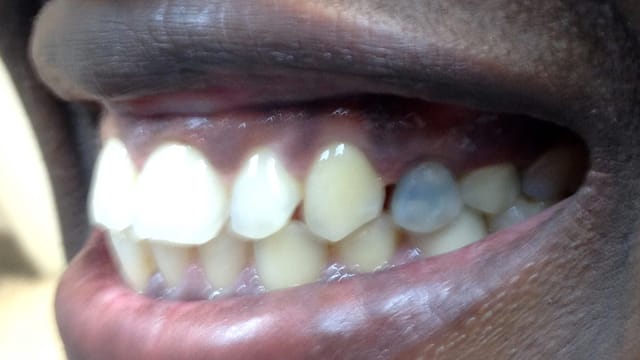

Below is a few examples of what DENTAL IMPLANTS can do for you and your smile!